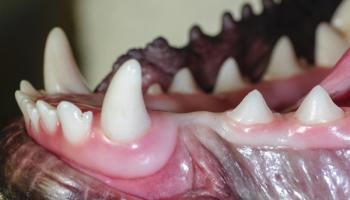

When it comes to dental care, sometimes immediate action is a must for your patient’s health and comfort.

On this episode of The Vet Blast Podcast Dr Adam Christman is joined by veterinary dentist Dr Jan Bellows, who shares several key ways to improve dentistry at your practice.